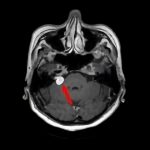

断層撮影

手術前1

手術前2